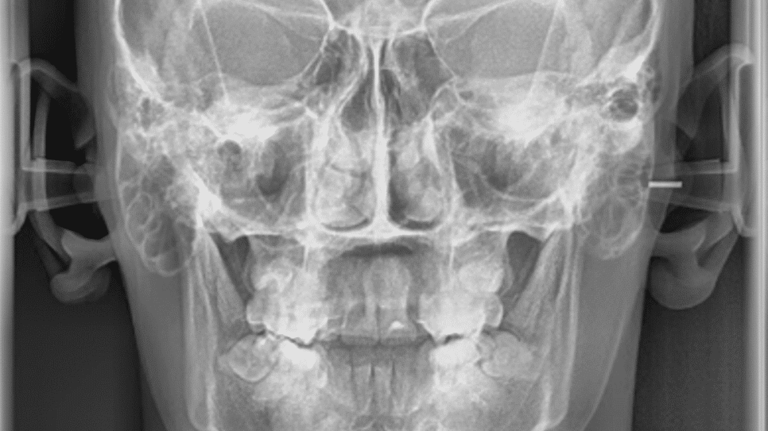

TELERRADIOGRAFIA FRONTAL